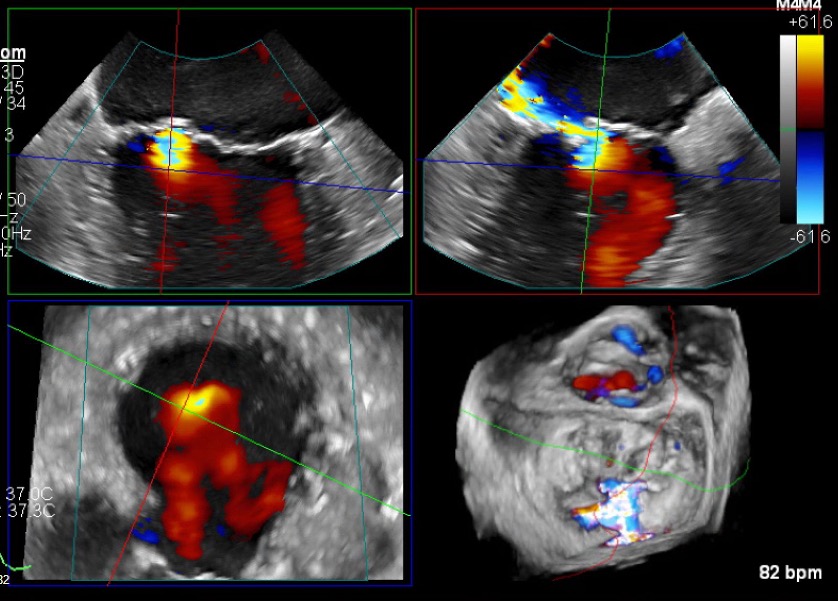

Fig. 5.

Transoesophageal echocardiography (TOE) 20 months from index admission. Top left: 4-chamber view demonstrates persistent mitral regurgitation. Top right: alternative 2D plane with colour doppler confirming a turbulent regurgitant jet directed into the left atrium. Bottom left: cross-sectional (short-axis) view with colour doppler showing the regurgitant jet spreading within the atrium. Bottom right: TOE 3D reconstruction displaying persistent mitral regurgitation.